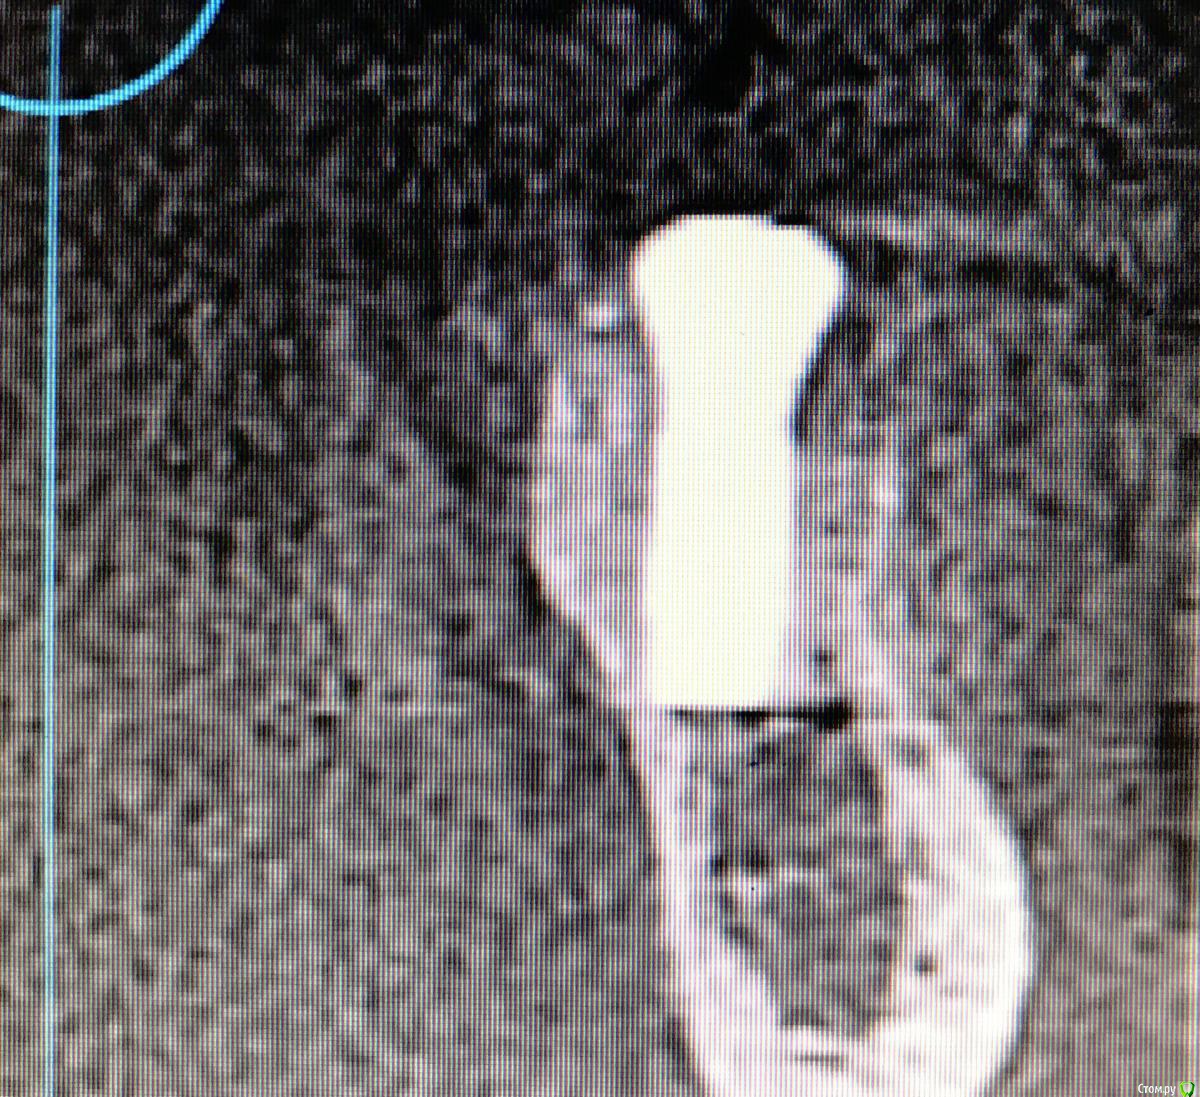

колесников Опубликовано 22 декабря, 2018 Автор Поделиться Опубликовано 22 декабря, 2018 Контроль просили. 1 пациент. Снимок майский,на тот момент 6-7 мес после вмешательства. Графтинг в обл имплантов и в промежутках ,3,4ый сектор 1 Ссылка на комментарий

колесников Опубликовано 16 февраля, 2019 Автор Поделиться Опубликовано 16 февраля, 2019 Спрашивали кт . Вид через 3-4 мес 1 Ссылка на комментарий

колесников Опубликовано 13 марта, 2019 Автор Поделиться Опубликовано 13 марта, 2019 Ну чтож, прошло 3 месяца,самое время посмотреть что там на кт. 1 Ссылка на комментарий